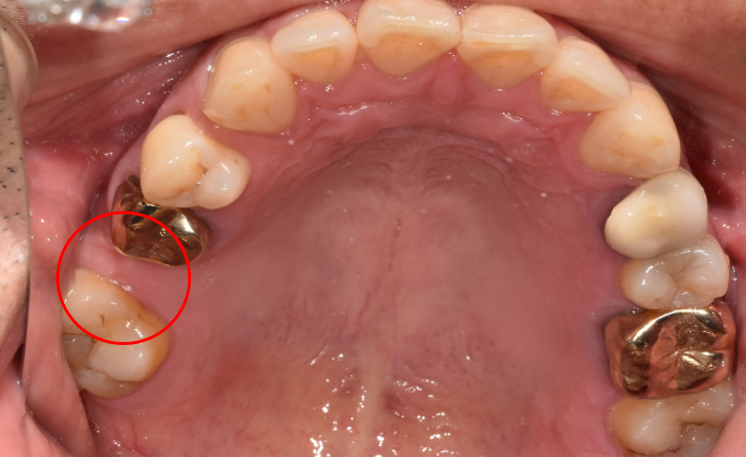

임플란트 전 Before & After

임플란트 시술에는 발치하고 나서 바로 식립하는 방법과 발치하고 얼마 정도 시간이 흐른 다음 식립하는 지연 식립이 있습니다. 바로 식립할 때는 발치하고 기다리는 시간이 없으므로 3개월 만에 치료를 마칠 수 있습니다.

이는 환자분들의 구강건강 상태와 치아 구조를 보고 식립 방법을 결정하게 됩니다. 구강상태가 좋지 않거나 치아가 약하다면 바로 식립하기보다는 지연 식립 방법으로 진행할 수 있습니다.

임플란트 치료는 자연치아와 가장 유사한 모양으로 구현해 내야 합니다. 디데이치과에서는 3D 기법을 활용해 네비게이션 임플란트 방식으로 치료를 도와드리고 있습니다.

다른 시술에 비해 네비게이션 임플란트는 환자 한 분 한 분에게 가장 알맞은 치아 구조 형태를 만들어낸다는 장점을 가지고 있습니다.